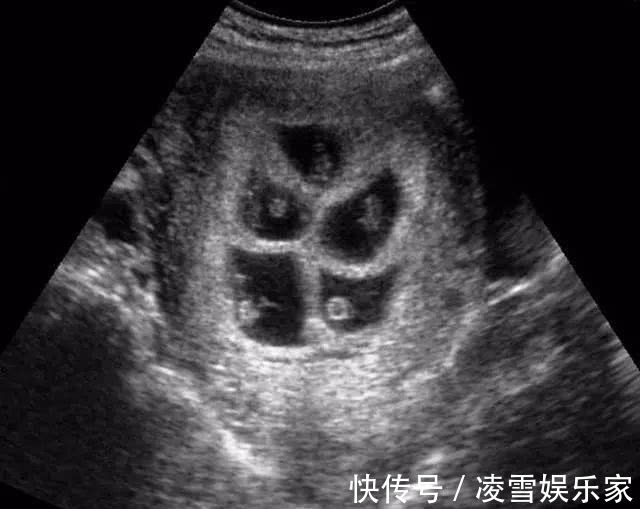

莉莉今年25岁,和老公是大学同学,两人毕业后就领证结婚了。婚后没多久,莉莉就欣喜地发现自己怀孕了,婆家人得知莉莉怀孕的消息都高兴极了,赶紧带着莉莉去医院做检查,经过检查,莉莉的确怀孕了,让一家子乐坏了。在怀孕第三个月时,莉莉的孕肚就比其他孕妇要大上一圈,婆婆还调侃莉莉怀的是双胞胎。去医院做产检后,医生惊讶的发现莉莉肚子里竟然有6个胎心,这也就是说莉莉怀了6胞胎!!听到医生的话后,婆婆和莉莉都被吓了一跳,原本以为怀的是双胞胎,却没成想怀的是6胞胎。

手术当天,产科医生就来了20多位,经过3个多小时的剖腹产手术,莉莉平安产下了6名可爱的宝宝。当医生看到孩子的性别后,不禁感叹道:“这才是真正的金六福啊。”原来莉莉生下了3男3女,一共3对龙凤胎